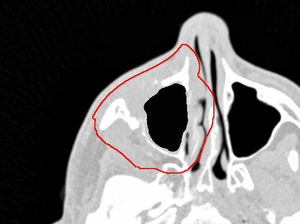

Når man skal optimere på et CTV, der inkluderer meget luft og knogle - f.eks. i sinonasal-området - kan det være svært at lave en robust plan i Eclipse.

- CTVer skal som udgangspunkt være uden luft, hvis der er luft i CTV så lav et oCTV uden luft.

- Accepter et max lidt over 110% det ligger ofte i luftkavitet og er lille.